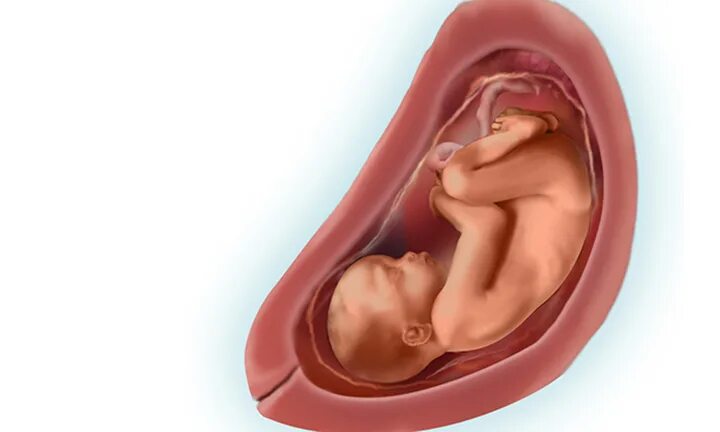

29 неделя ощущения